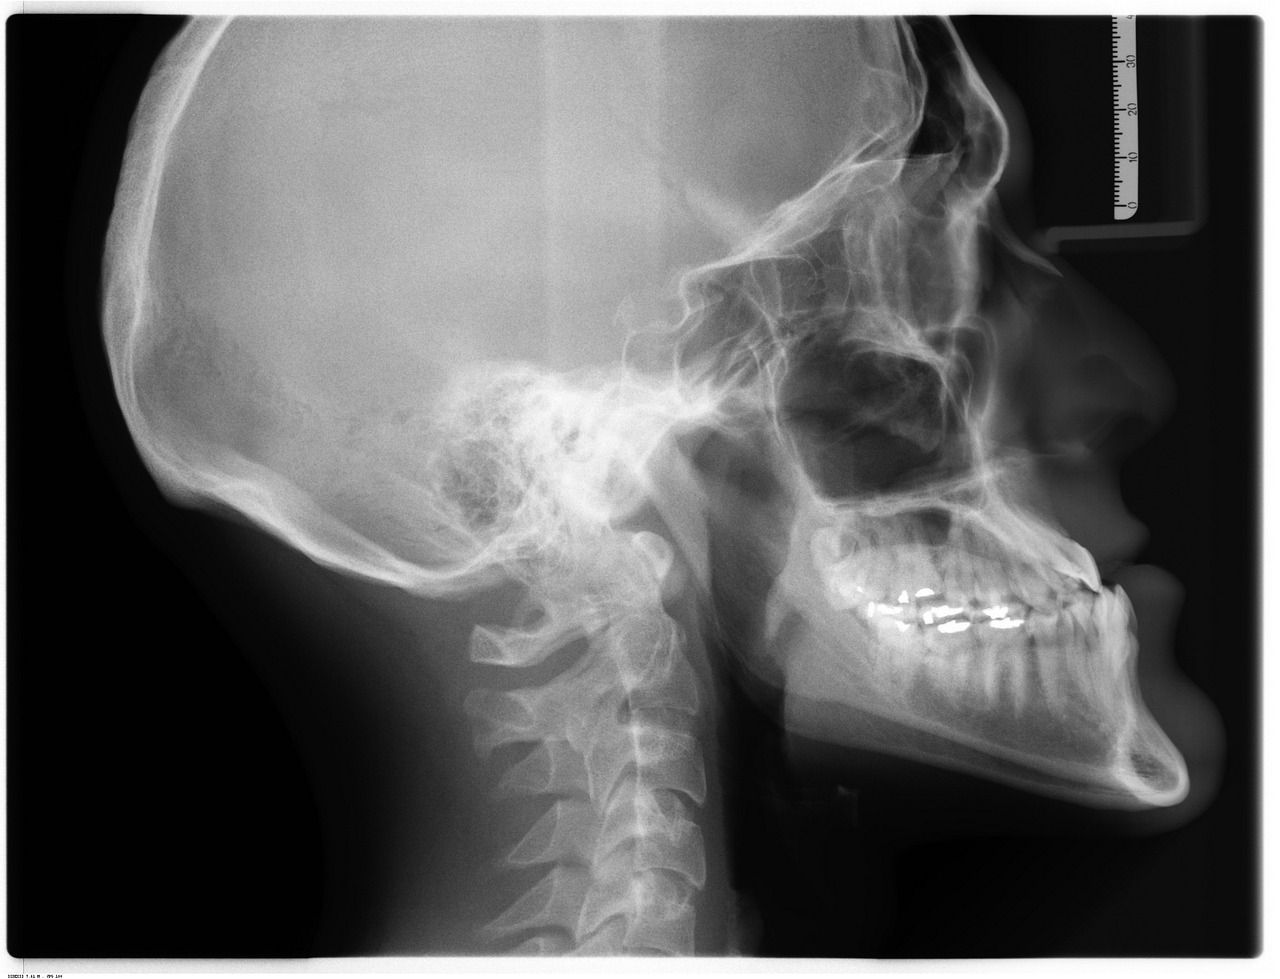

El ciclo formativo de TSID FP Imagen para el Diagnóstico y Medicina Nuclear no solo se centra en la teoría. Aquí, se valora la formación práctica como un pilar fundamental. Desde el primer día, te sumergirás en un ambiente de aprendizaje donde las tecnologías de diagnóstico son el pan de cada día.

- Laboratorios equipados con tecnología de última generación.

- Salas de prácticas que simulan entornos reales de trabajo.